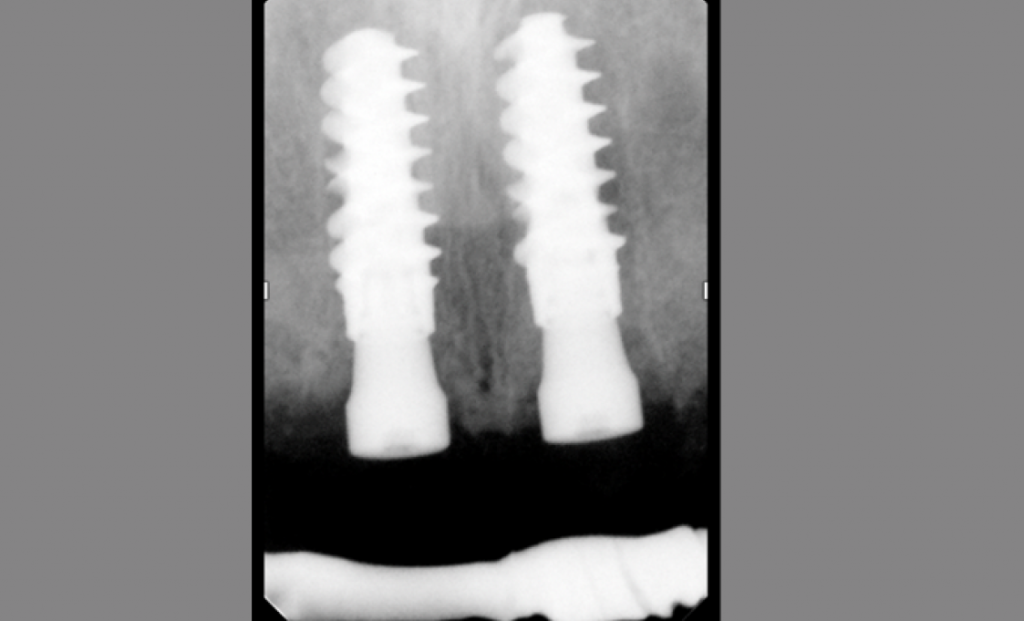

Этот пациент обратился ко мне с жалобами на сильную боль, покраснение и отек вокруг только что установленной коронки на имплантате. В анамнезе было следующее: был снят аналоговый оттиск с уровня имплантата и отправлен в лабораторию для изготовления коронки. У лаборанта не было указаний относительно расположения шейки имплантата по отношению к мягким тканям и кости.

Была выбрана самая короткая высота десневой манжеты (GH), так как она является наиболее безопасной с эстетической точки зрения, поскольку металлическая кромка не будет видна над десной. При доставке коронки на имплантат стоматолог столкнулся с трудностями при «посадке» коронки на абатмент.

Коронка была установлена со значительным сопротивлением для достижения необходимого значения торка. Ущемление твердых и мягких тканей из-за очень острого профиля выступа вызывает давление на кость, что приводит к некрозу и, в конечном итоге, к потере маргинальной кости в этой области. Чтобы избежать подобных осложнений, необходимо выбирать правильный абатмент.